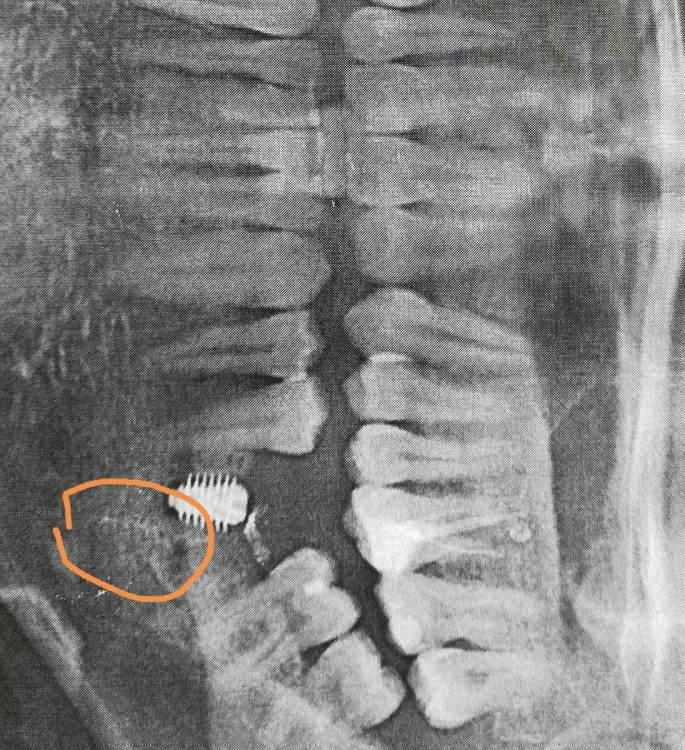

Nik-E Опубликовано 11 октября, 2021 Поделиться Опубликовано 11 октября, 2021 Здравствуйте. Нужно мнение специалистов. Была проведена имплантация, сделан снимок, на снимке непонятное пятно как будто похожее на резьбу, до установки импланта такого пятна не было. Что это за пятно может быть? И правильно ли установлен имплант? Заранее спасибо. На снимке я место с пятном выделил. Ссылка на комментарий

Irouil Опубликовано 11 октября, 2021 Поделиться Опубликовано 11 октября, 2021 Рекомендую показать этот снимок ортопеду, который будет Вас протезировать. Там, где Вы отметили, все в порядке Ссылка на комментарий